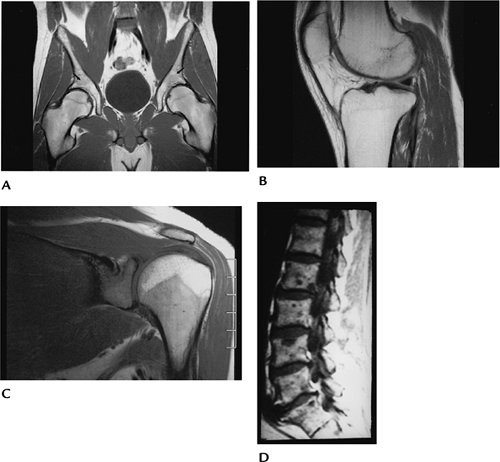

ffbc877f785f656b01216fb6a85c3f13.png

图-5髋关节缺血性坏死。T1像显示缺血性坏死,左侧更为严重。

816fffc5d8097e533c37f9acac40b5e5.png

图-6骨梗死。双膝站立位X光片显示双膝典型骨梗死的蛇行状边缘钙化。T1WI显示了梗死区和软骨下缺血性坏死。